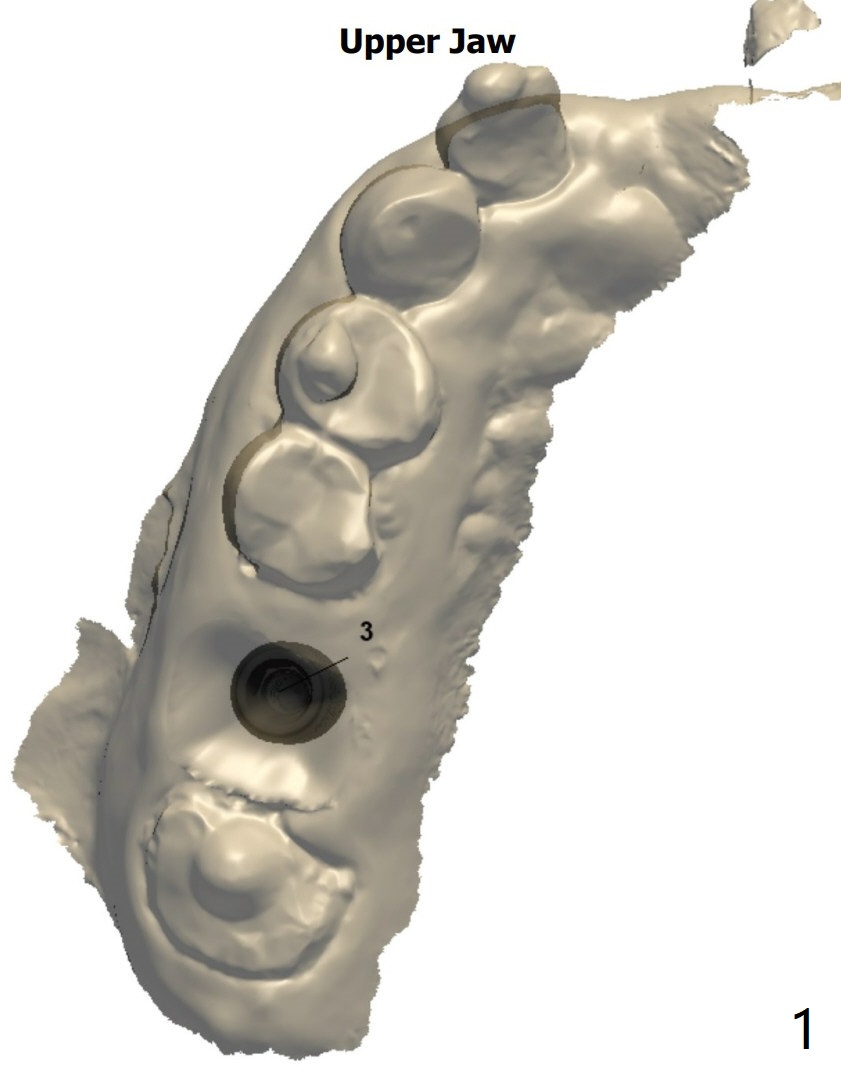

Use 5x10 mm Dummy Implant for Sinus Lift ~1.5 mm short of 1st line

A 67-year-old woman has dislodged #3 and #2 crowns. The former is lost, while the latter is short. The tooth #3 has severe bone loss. After immediate implant and immediate abutment, consider splint #2 and 3 temporary crowns for retention.